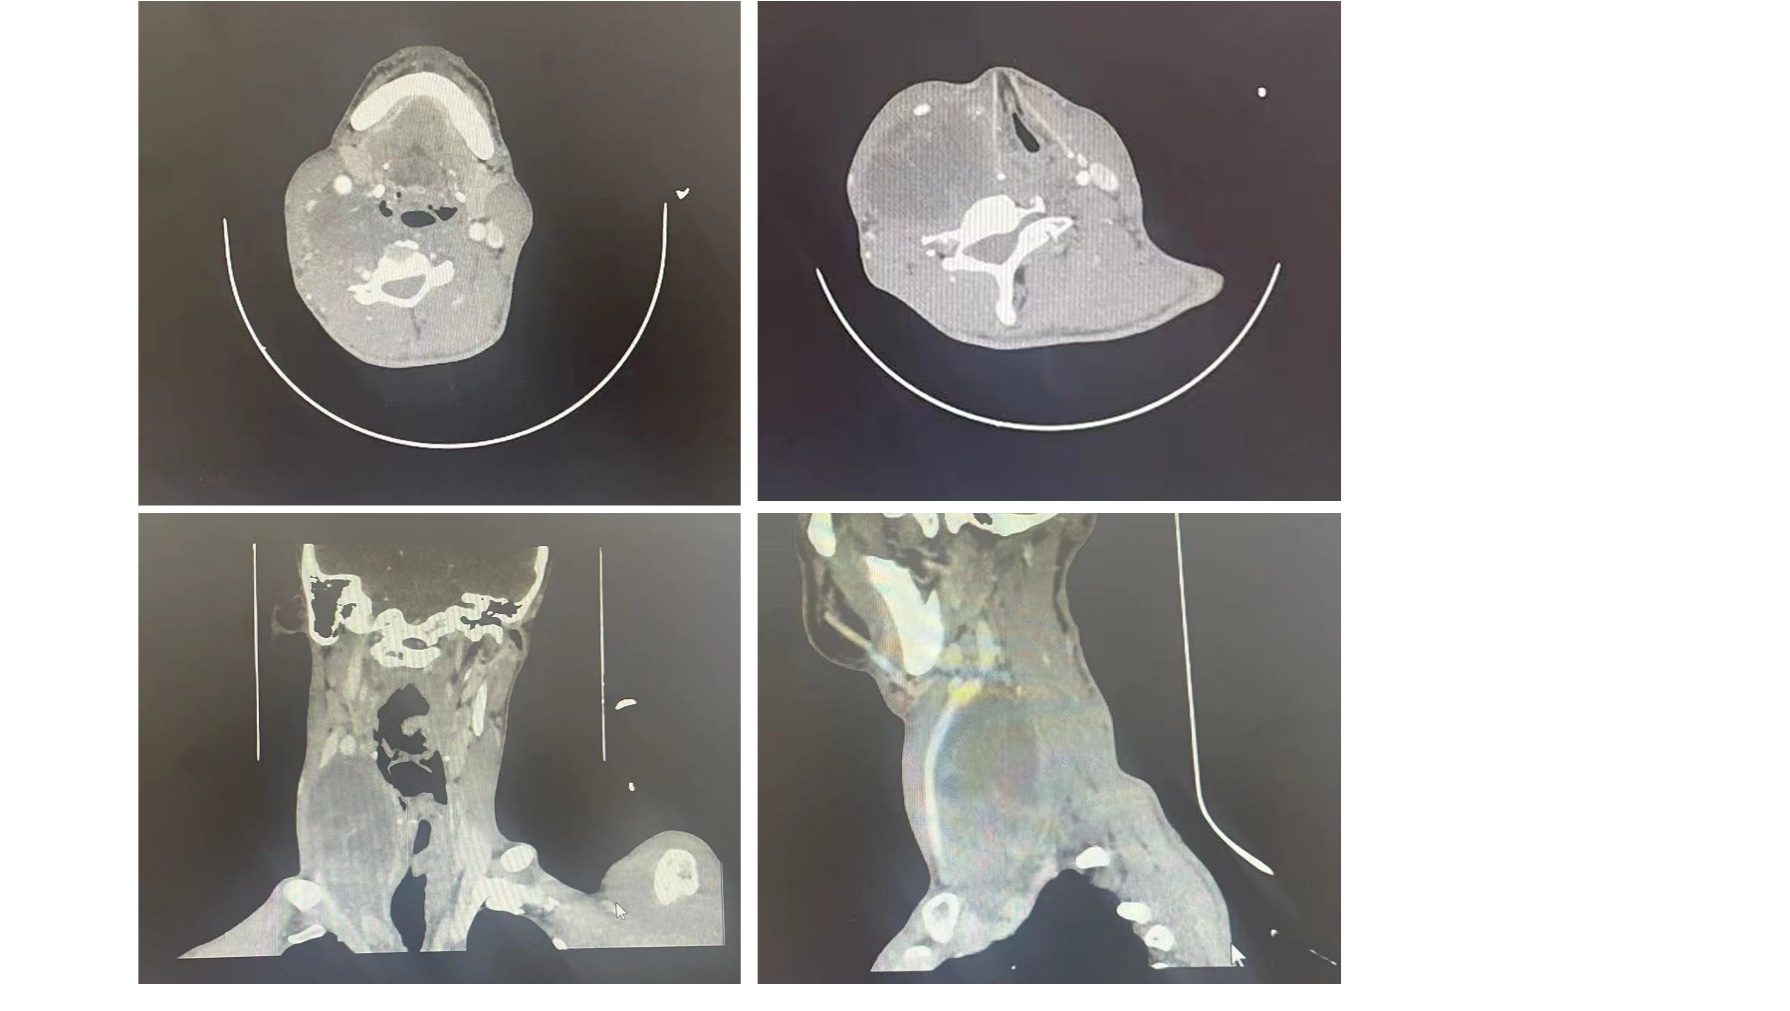

经过甲状腺头颈外二科医疗团队的全面检查,查体可见其颈部不对称,右侧颈可见一隆起性肿物,大小约10×5cm;彩超显示其右侧甲状腺后方可见一大小约9.5×4.8cm囊实回声;增强CT可见右颈部间隙多房状软组织影,上缘达舌骨右支咽旁水平,下缘至右侧锁骨下动脉上缘水平,内侧缘至甲状软骨板外侧缘,外侧缘与右侧胸锁乳突肌分界不清。气管受压左移,肿物与右颈内静脉分界不清,右颈总动脉移位至肿物前方。结合患者临床表现及影像学检查,初步考虑为神经鞘瘤可能性大。但患者有神经纤维瘤病史,不除外神经纤维瘤恶变可能,且肿物范围较大,与血管分界不清。瘤体不但影响外观,还对患者身体造成沉重负担,严重影响正常生活,针对患者在多家色情导航

诊治的特殊情况,结合影像学检查,汪晓春主任多次组织全科及多学科联合会诊,就肿块是否为恶性、手术入路、肿块安全切除范围等进行了反复讨论,在避免损伤颈部肿块下方的副神经、膈神经、臂丛、迷走神经前提下,还要完整切除正常肌肉组织构成的假包膜等方面团队制定了严密的手术计划,由汪晓春主任主刀,为这名患者进行了手术,术中于肿物前方可见移位的右侧颈总动脉及颈内静脉,颈内静脉全程及颈总动脉肩胛舌骨肌处与肿物粘连严重,锐性及钝性全程分离颈总动脉及颈内静脉。肿物高度浸润右侧迷走神经,遂离断右侧迷走神经。逐步分离肿物周围组织,历时3小时余,团队在主任汪晓春、副主任殷向党的带领下,成功将肿物完整切除。术后患者恢复良好,上肢运动正常,无明显不适主诉。术后石蜡病理回报诊断为恶性外周神经鞘膜瘤。患者生命体征平稳,切口甲级愈合。